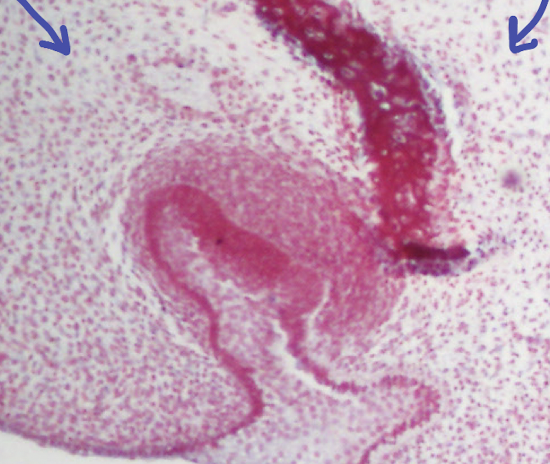

ID the red in the center

A

What is this process?

Intramembranous ossification

Q

Is this young/woven or mature/lamellar?

Young